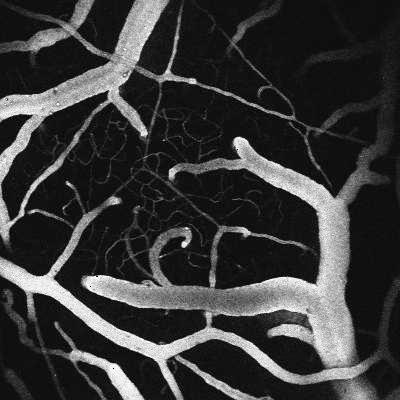

Mesh-like network of arteries adjusts to restore blood flow to stroke-injured brain

A grid of small arteries at the surface of the brain redirects flow and widens at critical points to restore blood supply to tissue starved of nutrients and oxygen following a stroke, a study published this week has found.

Key to this resilience, it seems, is the structure of the vascular network overlying the brain.

"Vessels on the surface of the brain have a mesh-like architecture," Kleinfeld said. "One consequence of that is that it operates like a grid system that redistributes "current flow as you need it."

Flows through the surface vessels reversed and stalled, as previously observed, but those changes helped to redistribute blood to ensure a steady supply though vessels that penetrate into the brain.

Shih focused his measurements on small arteries, called arterioles, at the point where they dive into the brain to supply a discrete patch of the cortex, a juncture that is vulnerable to occlusions that can cause microstrokes this group's previous work has found.

"These are extremely important. A single penetrating arteriole will feed a column of tissue," Shih said. "These are bottlenecks in flow."

The penetrating vessels neither reversed nor stalled, even though many connected to loops and bridges in the vascular network that could have allowed that to happen. Even when the pressure dropped permanently as a result of stroke damage, wider lanes allowed the network to deliver red blood cells at the same rate.

"Diameter is the major determinant to how blood actually flows through vessels. Open up a blood vessel a little bit and you'll have a huge change in the amount of blood that goes through," Shih said. "Blood flow comes back, and it seems that these vessels are very resistant to the stroke. They function quite normally."